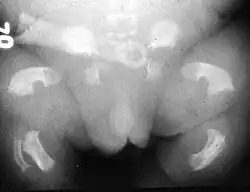

![]() Rafiografía de un recién nacido afecto de enanismo tanatofórico | ||

El enanismo tanatofórico, también llamado displasia tanatofórica, es una rara enfermedad de origen genético que afecta al desarrollo del esqueleto y se incluye dentro del grupo de trastornos conocidos como osteocondrodisplasias. Provoca anomalías que afectan a diferentes huesos, incluyendo miembros muy cortos, deformidades del tórax, costillas cortas y cabeza aumentada de tamaño (macrocefalia), con longitud del tronco normal. El pronóstico es malo, produciéndose generalmente la muerte intraútero antes del nacimiento.[1][2]

Existen 2 subitipos, el 1 con fémures curvados y el 2 con fémures no curvados y cráneo con forma característica en hoja de trébol.